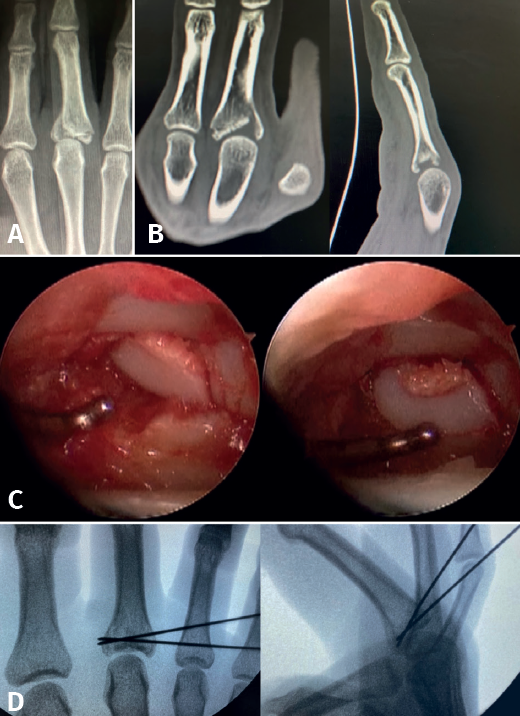

As with Bennett fractures of the thumb, fractures involving the articular surface, both of the common metacarpal head (less commonly) and of the base of the proximal phalanx, can be evaluated and treated with an arthroscopically assisted approach(9).

There are authors who divide the joint fractures into two groups(1):

- Fractures with avulsion of the insertion of the collateral ligament (Figures 2 and 3).

- Intra-articular fractures proper, caused by compression or shear mechanisms.

The main fragments are reduced with the aid of a palpator or a small blunt dissector. External reduction of the fragments may be necessary, especially when they are impacted in the centre of the articular surface. This is especially common at the base of the proximal phalanx. To do this, we introduce a 1.0 Kirschner wire through the fracture site, through an extra-articular "window", and in "joystick" fashion, we lower the impacted fragment. Sometimes it is advisable to check each of the maneuvers using fluoroscopy, which can be positioned perpendicular to the arm or in the traditional manner, which requires us to release the hand of the patient in order to perform the check.

In some cases it is necessary to insert a spongy graft through the fracture site to maintain reduction and thus avoid joint step-off.

Once the fragments have been reduced, 0.8 or 1.0 Kirschner wires are used to maintain reduction (Figure 7). Sometimes we can only maintain reduction by applying a stop, to prevent the osteochondral fragment from collapsing. Depending on the fracture pattern and the surgeon's preference, we can use conventional screws, cannulated screws, etc. (Figures 8 and 9).